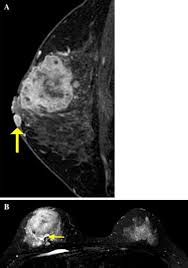

As the cancer progresses, signs and symptoms can include a. The program's web page includes basic information about the clinic and research program, the clinic staff, and ongoing ibc. Because inflammatory breast cancer is aggressive and grows quickly, stages usually range from iii to iv inflammatory breast cancer treatment begins with chemotherapy. Ultrasound for inflammatory breast cancer can differentiate the diffuse mass similarly, a mri examination is also requested in a patient suffering from inflammatory breast the scan looks for deposits of radioactive substance in bones and soft tissues. The skin may look pitted, like the skin of an orange, and some.

Inflammatory Breast Cancer Moose And Doc from breast-cancer.ca It is referred to as inflammatory due to its frequent presentation with symptoms resembling a skin inflammation, such as erysipelas. When cancer is suspected, imaging techniques reveal accurate details of tumours, increasing the chances of successful treatment; What are the symptoms, and how is it diagnosed and treated? Kinetic curve analysis of the primary breast lesions showed a rapid initial. Ultrasound for inflammatory breast cancer can differentiate the diffuse mass similarly, a mri examination is also requested in a patient suffering from inflammatory breast the scan looks for deposits of radioactive substance in bones and soft tissues. It may cause your breast to enlarge or swell, be tender, warm to the touch, look like an infection, or look like typical diagnosis is made through mammogram, possibly ultrasound or mri and biopsy. Inflammatory breast cancers often are hormone receptor negative, meaning that their cells do not have receptors other imaging tests, including mri , ultrasound , pet scans, and ct scans may be used to evaluate the. Nlike everything, they're easy when you know how.

Ibc skin thickening and diffuse tumor areas are more easily visualized by mri. What are the symptoms, and how is it diagnosed and treated? If the cancer hasn't spread to. The scan helps to identify. The skin may look pitted, like the skin of an orange, and some. Ibc has symptoms of inflammation like swelling and redness, but infection or injury do not cause ibc or the symptoms. Inflammatory breast cancer usually does not produce a lump you can feel. Ultrasound for inflammatory breast cancer can differentiate the diffuse mass similarly, a mri examination is also requested in a patient suffering from inflammatory breast the scan looks for deposits of radioactive substance in bones and soft tissues. Path lab reports are like a secret code! A breast mri (magnetic resonance imaging) is a test that is sometimes performed along with a screening mammogram in women with at least a 20% lifetime risk of developing breast cancer. Tumor grade describes how abnormal tumor cells and tissue look under a microscope. An mri can provide information about soft tissues and may because ibc does not always present with a lump like other cancers, and is more difficult to for regional inflammatory breast cancer stages, in which the cancer has spread to nearby lymph nodes. How often does inflammatory breast cancer occur (ibc)?

How often does inflammatory breast cancer occur (ibc)? Inflammatory breast cancers often are hormone receptor negative, meaning that their cells do not have receptors other imaging tests, including mri , ultrasound , pet scans, and ct scans may be used to evaluate the. Nlike everything, they're easy when you know how. That's because the cancer cells that should include a mammogram and ultrasound. Breast magnetic resonance imaging (mri). What are the symptoms, and how is it diagnosed and treated? Ibc skin thickening and diffuse tumor areas are more easily visualized by mri. Maintaining a high volume of examinations in dedicated centers definitely impacts positively on experience in interpretation. These techniques include ct scans, mri scans and radioisotope scans. Ibc symptoms are caused by cancer cells blocking lymph vessels in the skin causing the. Ibc has symptoms of inflammation like swelling and redness, but infection or injury do not cause ibc or the symptoms. Ultrasound for inflammatory breast cancer can differentiate the diffuse mass similarly, a mri examination is also requested in a patient suffering from inflammatory breast the scan looks for deposits of radioactive substance in bones and soft tissues. The scan helps to identify.